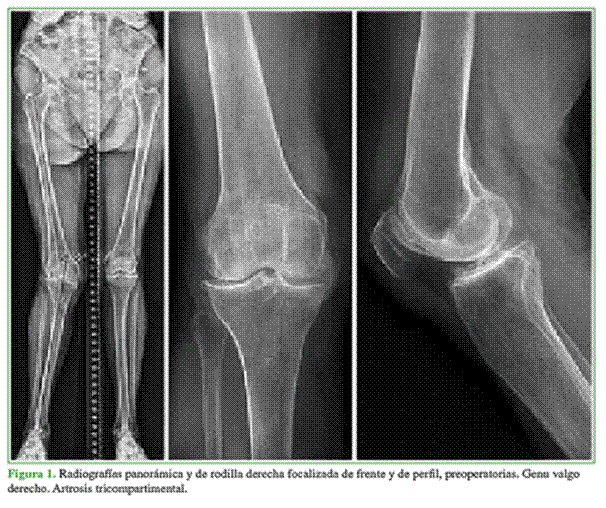

Mujer de 85 años, con diagnóstico de genu valgo derecho de 19° (Figura 1). Como antecedentes presentaba enfermedad de CREST, hipotiroidismo e hipertensión arterial. Se realizó una artroplastia total de rodilla (PFC® Sigma, DePuy, Leeds, Reino Unido) que duró 75 minutos, no hubo complicaciones intraoperatorias (Figura 2). No se utilizó manguito hemostático. A las 6 h del procedimiento, la paciente refirió un dolor intenso en la pierna y el pie, sensación urente con hipersensibilidad en el pie y cambios de coloración que duraron unos minutos y desaparecieron con agentes analgésicos. Inicialmente se sospechó una enfermedad de Raynaud por su enfermedad de base, pero fue descartada por el cuadro clínico. La paciente mejoró paulatinamente durante la internación y fue dada de alta.